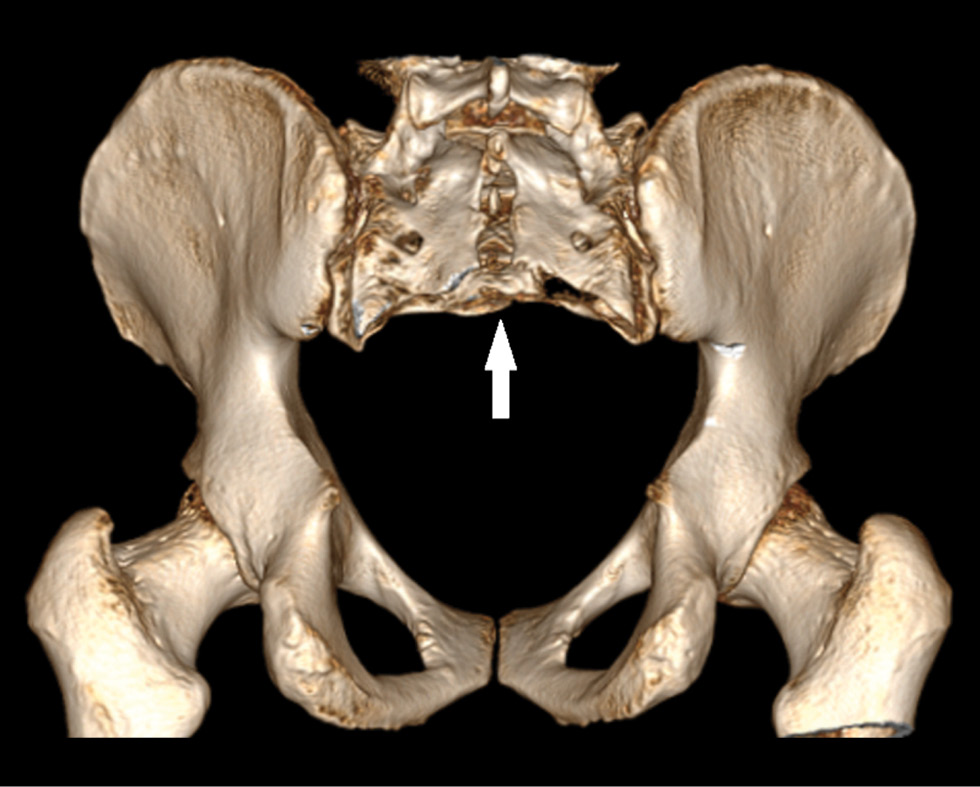

Fig. 8. Three-dimensional CT reconstruction after surgery, posterior view. Resection of the sacrum at the level of the S3 vertebra (arrow).